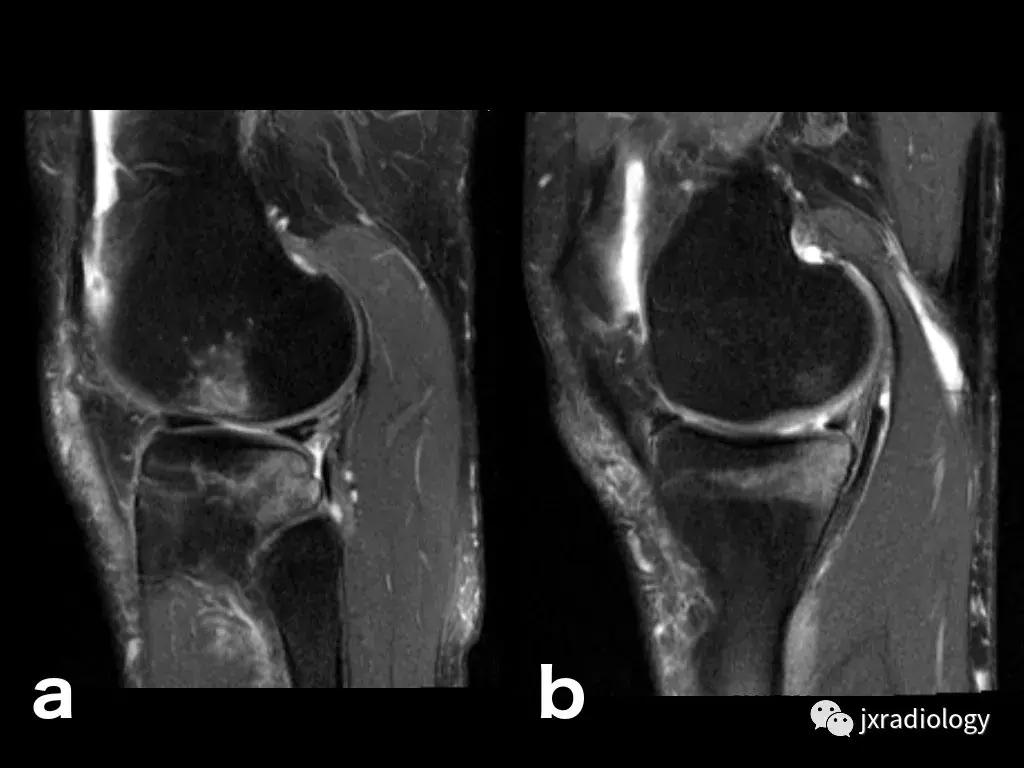

图26:局限性游走性骨质疏松症(具有位置变化的短暂性骨髓水肿综合征)(连续冠状PD-FS-WI):在一些情况下,在连续MRI上看到骨髓水肿的位置变化,这被称为局限性游走性骨质疏松症(RMO);尽管可以自愈的短暂性骨髓水肿综合征的情况更为常见,但可以在一小部分病例中转移到不同的关节,或者(甚至更罕见)转移到同一关节内的不同部位(关节内转移) ,如关于该患者所见。在这个关节内RMO病例中,没有创伤史,水肿始于股骨内侧髁,3个月后发现转移到外侧髁。